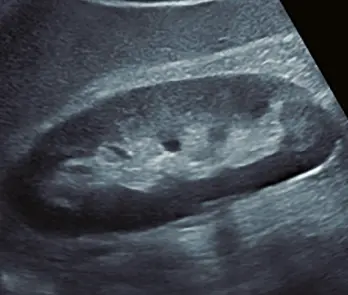

Fig: 10

Fig: 10, imagen papilar (flecha) dentro de una formación quística.

Fig: 11

Fig: 11, formación nodular ecogénica dentro de una imagen quística (flecha).